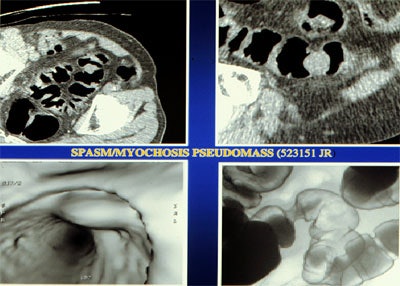

The presence of myochosis can make it difficult to distinguish muscular disease from neoplasm, whether in 2-D or 3-D views, he said. For example, if the 3-D view shows a bulging mass in the lumen that can't be identified on CT, sometimes evaluation can be made using double-contrast barium enema "by characterizing the area as a more gradual contraction without proof of any borders, and, more importantly, in the preservation of the mucosa," he said. "This is one of the few times where we think CT shows us too much information and confuses us."

| Top left: prone oblique CT scan of pelvis during virtual colonoscopy showing muscular thickening in sigmoid colon. Top right: multiplanar reformatted image through muscle abnormality (myochosis) simulating a mass. Bottom left: Virtual colonoscopic view of "mass." Bottom right: double-contrast barium enema shows that "mass" is only spasm. Images courtesy of Dr. Marc Gollub. |

"Myochosis is a morphologic feature of diverticular disease which limits the quality of virtual colonoscopy in the sigmoid colon," Gollub said during his presentation. "Patients with myochosis, with or without diverticula, displayed significantly less sigmoid distension. So we feel that in patients with diverticular disease with myochosis, evaluation of the sigmoid may be limited on VC, and if patients had an incomplete colonoscopy, for example, maybe they should get another test such as the double-contrast barium enema. But VC is still an appropriate examination to look at the remainder of the colon."